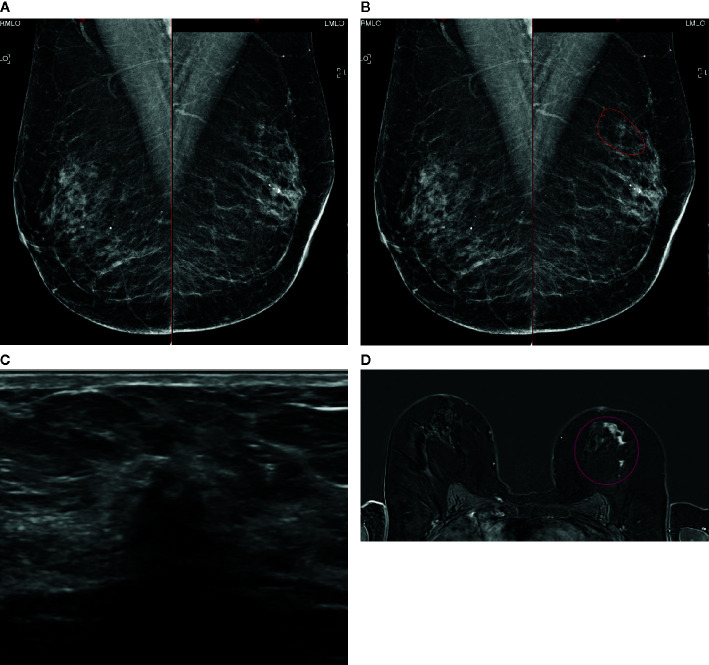

Figure 5.

A case of extensive ILC in a 50-year-old female attending for 1st breast screening. (A) Mammogram: Right and left MLO views. (B) Mammogram is reported as M3. There is a 5-mm area of concern on the left which is circled. The calcifications are considered benign. The patient does not feel a palpable mass. (C) An US of the left breast is performed and shows a small 8mm focus close to the nipple. (D) MRI breast follows and this shows an extensive area measuring approximately 50 mm × 50 mm (circled). Biopsies were performed and showed Gr2 ILC ER8 PgR8 HER negative. Patient had mastectomy and sentinel node biopsy (SNB) that showed 52-mm Gr2 ILC ER8 PgR8 HER2 negative SNB 0/3. (A) Mammogram: Right and left MLO views (B) Mammogram M3: possibly a 5-mm area of concern on the left (circled). Calcifications look benign. (C) Ultrasound: One small focus closer to nipple maybe 8mm. (D) MRI: Extensive central disease over 50 mm × 50 mm (circled).